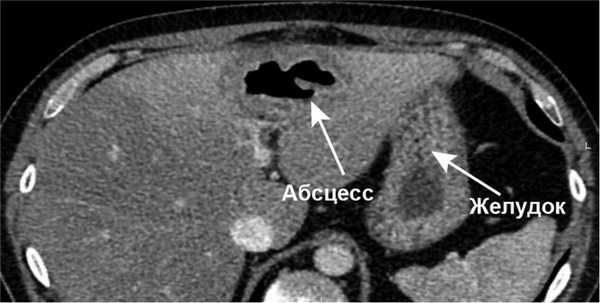

Результаты лабораторных исследований: лейкоциты (WBC) 11,7·10 9 /л; гемоглобин (HGB) 134 г/л, биохимический анализ крови — без отклонений от нормы. Начато проведение антибактериальной терапии (ципрофлоксацин 400 мг 3 раза в день в/в, метронидазол 500 мг 3 раза в день в/в). Учитывая неясный генез образования абсцесса, с целью дообследования была выполнена КТ органов брюшной полости с в/в болюсным усилением, по результатам которого выявлено инородное тело, располагающееся в передней стенке выходного отдела желудка (рис. 1, 2), размерами 30×2 мм с пенетрацией в паренхиму S3 печени и формированием абсцесса 45×35×30 мм (рис. 3, 4).

Рис. 4. Пациент П. КТ органов брюшной полости в венозную фазу, аксиальный срез. Визуализируется абсцесс печени.